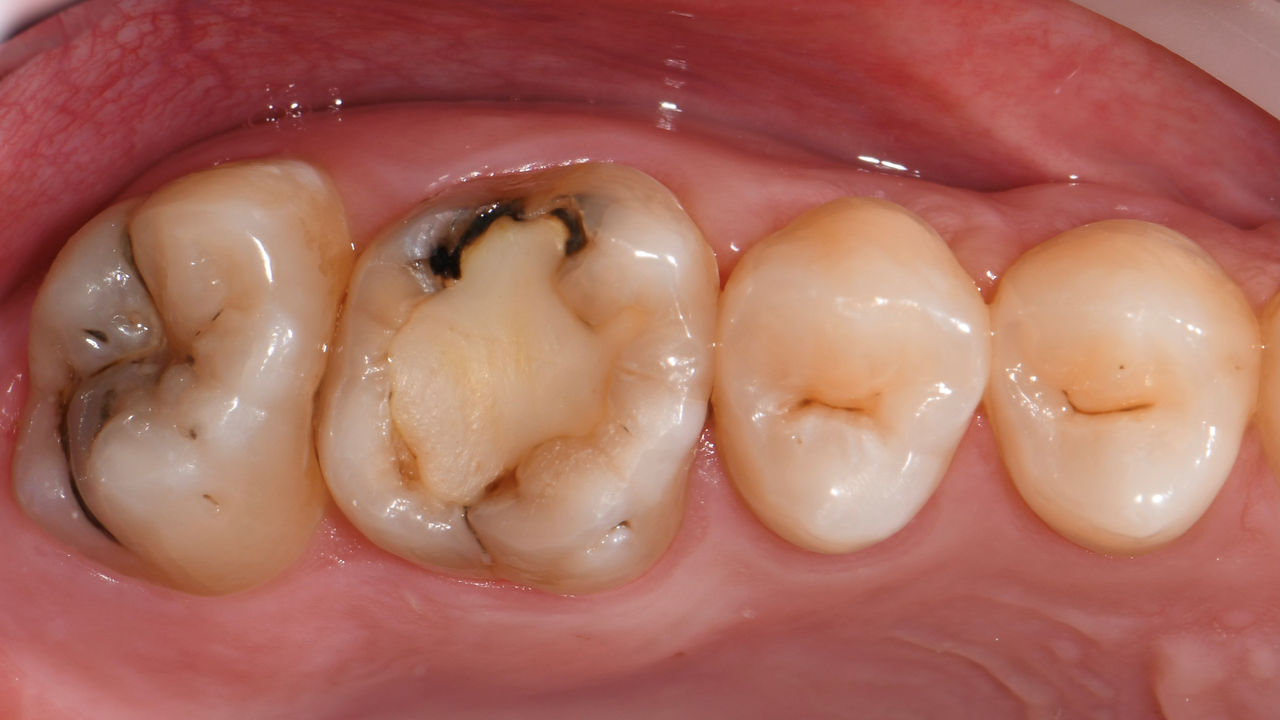

Restauration de la deuxième molaire mandibulaire en consultation

Couronne partielle CEREC Tessera

Une deuxième molaire mandibulaire sensible présentait des fissures ainsi qu’une restauration composite de classe I étendue sur la face vestibulaire. Conformément au concept mini-invasif, une couronne partielle CFAO a été planifiée, fabriquée et collée à l’aide du CEREC Tessera en une seule visite.

Avant : Restauration en amalgame défaillante nécessitant un remplacement. Patient se plaignant de sensibilité et dent présentant de multiples fissures.

Après : Restauration d’une couronne partielle CFAO réalisée en consultation avec la vitrocéramique CEREC Tessera Advanced Lithium-Disilicate.